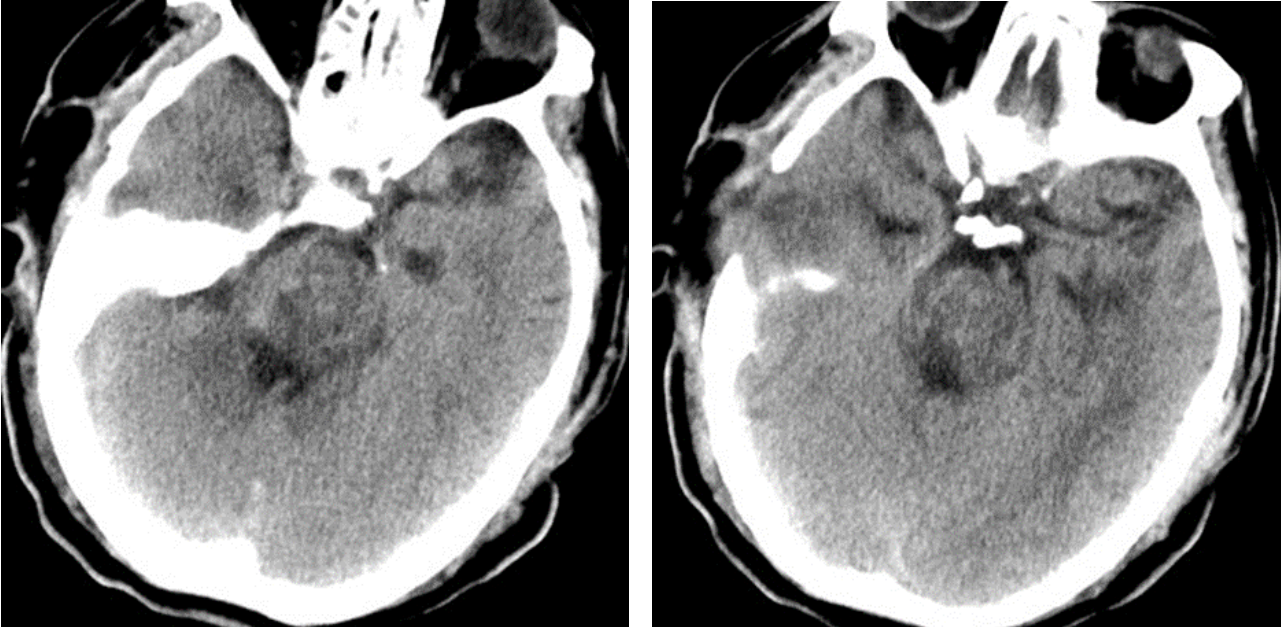

在手術(shù)室、麻醉科的積極配合下,整個手術(shù)團隊分工有序、緊密配合,采用顳下入路,切開小腦幕,暴露并保護滑車神經(jīng)、三叉神經(jīng)、大腦后動脈,應(yīng)用顯微鏡在橋腦三叉神經(jīng)上區(qū)域通過4毫米的通道,清除腦干內(nèi)10余毫升出血,并對原發(fā)出血部位妥善止血。經(jīng)過3個多小時的精細操作,在確保最小腦損傷的情況下清除血腫,術(shù)中各項監(jiān)測指標(biāo)平穩(wěn),術(shù)后復(fù)查頭顱CT顯示血腫清除滿意。術(shù)后經(jīng)過重癥監(jiān)護室積極治療,患者平穩(wěn)渡過中樞性高熱、嚴重肺部感染、營養(yǎng)低下等并發(fā)癥期,各項生命體征逐步平穩(wěn),對外界刺激有適當(dāng)反應(yīng),術(shù)后13天轉(zhuǎn)入普通病房繼續(xù)康復(fù)促醒治療。

術(shù)后患者顱腦CT: